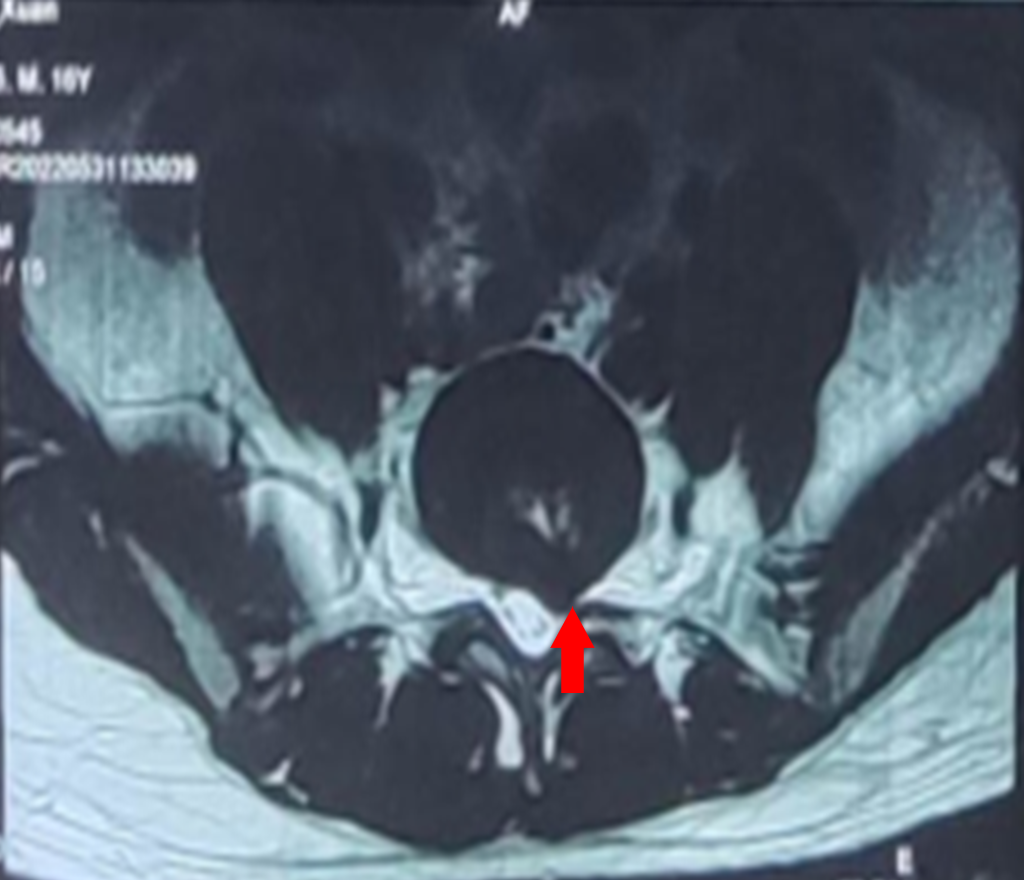

在家人的陪同下,小祁到家附近医院就诊,经腰部椎磁共振检测发现,小祁腰5/骶1椎间盘左后突出。

据了解,急性外伤是腰椎间盘突出的诱发因素,可导致椎间盘发生破裂,髓核、纤维环甚至终板向后突出,严重者压迫神经产生症状。由于长期运动姿势不良,加上3个月前意外受伤,在两者的共同作用下,最终导致小祁腰椎间盘突出。